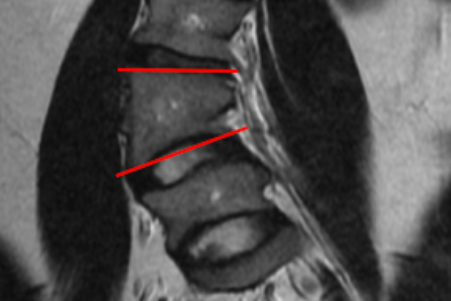

Hemivertebra Morphometry (wedge angle, segmentation)

MRI Scan